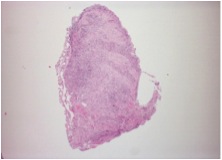

Excisional biopsy of submandibular gland with a diagnostic testing was performed. It showed lymphoid infiltrate with marked atrophy and perilobular and septal sclerotic fibrosis. The lymphoid infiltrate mainly consisted of small lymphocytes and large number of plasma cells. Immunohistochemical studies found most of the plasma cells positive for IgG and IgG4. So, the pathology suggested chronic sclerosing sialadenitis, consistent with IgG4-related disease. The ampulla specimen obtained in previous ERCP was also positive in IgG4 staining. The serum IgG4 level was checked and elevated to 102.9 g/L (normal range <2).

We reviewed the case and requested IgG4 staining for the transbronchial biopsy that obtained 3 months ago. The resulted showed many of the plasma cells positive cytoplasmic staining for both IgG and IgG4 (Fig 4A, 4B, 4C, 4D). It confirmed the pulmonary involvement of IgG4-related disease.